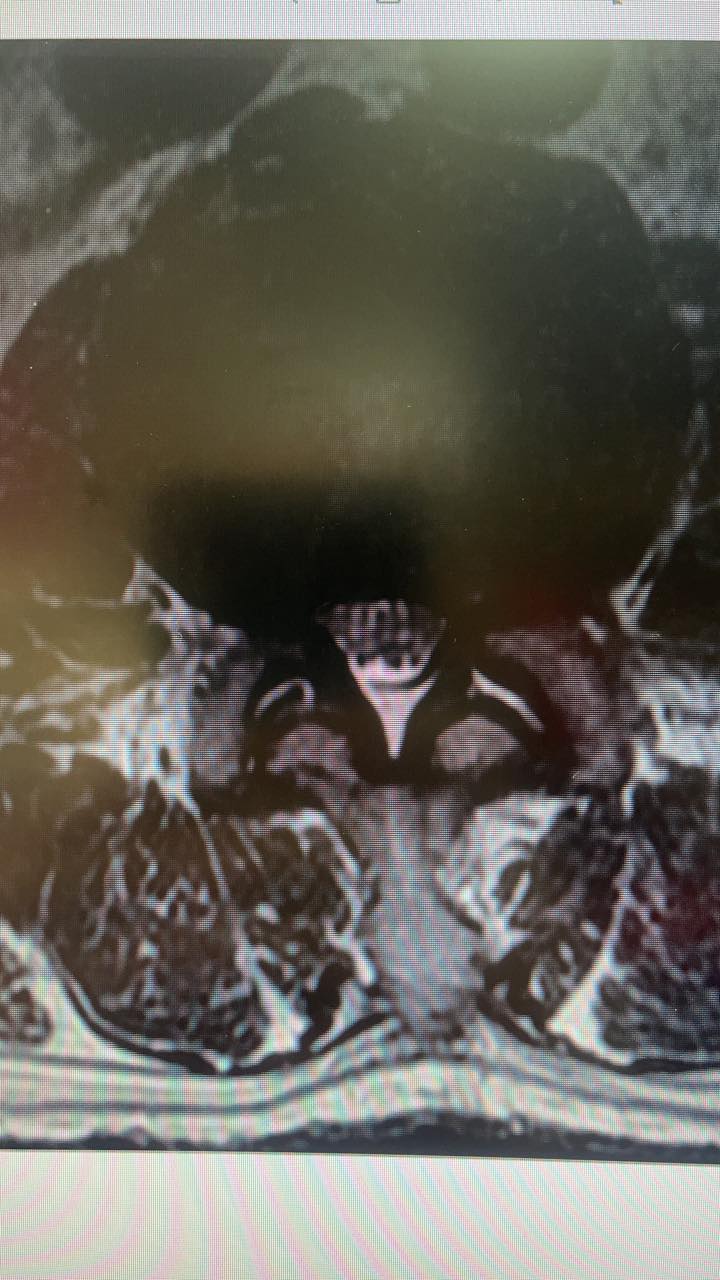

PS.原本腰痛到差點輕生的患者,很難想像腰椎嚴重狹窄會把人折磨到不成人形,體重暴瘦七公斤 !